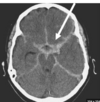

What does the CT depcit? Epidural haematoma Subarachnoid haematoma Subdural haematoma Intracranial haematoma

What does the CT depcit? Epidural haematoma **Subarachnoid haematoma** Subdural haematoma Intracranial haematoma